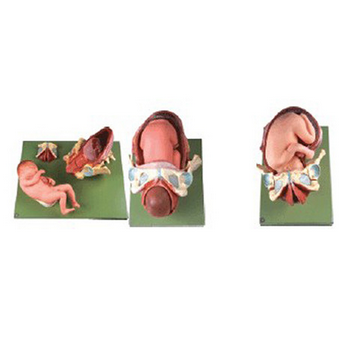

GD/A42007足月胎兒分娩過程模型產品介紹:1、該模型由骨盆、子宮、產道、足月胎兒、胎盤、臍帶等結構組成。顯示胎位、分娩過程(第一、二、三產程)共有44個部位指示標志。2、材質:進口PVC材料、進...